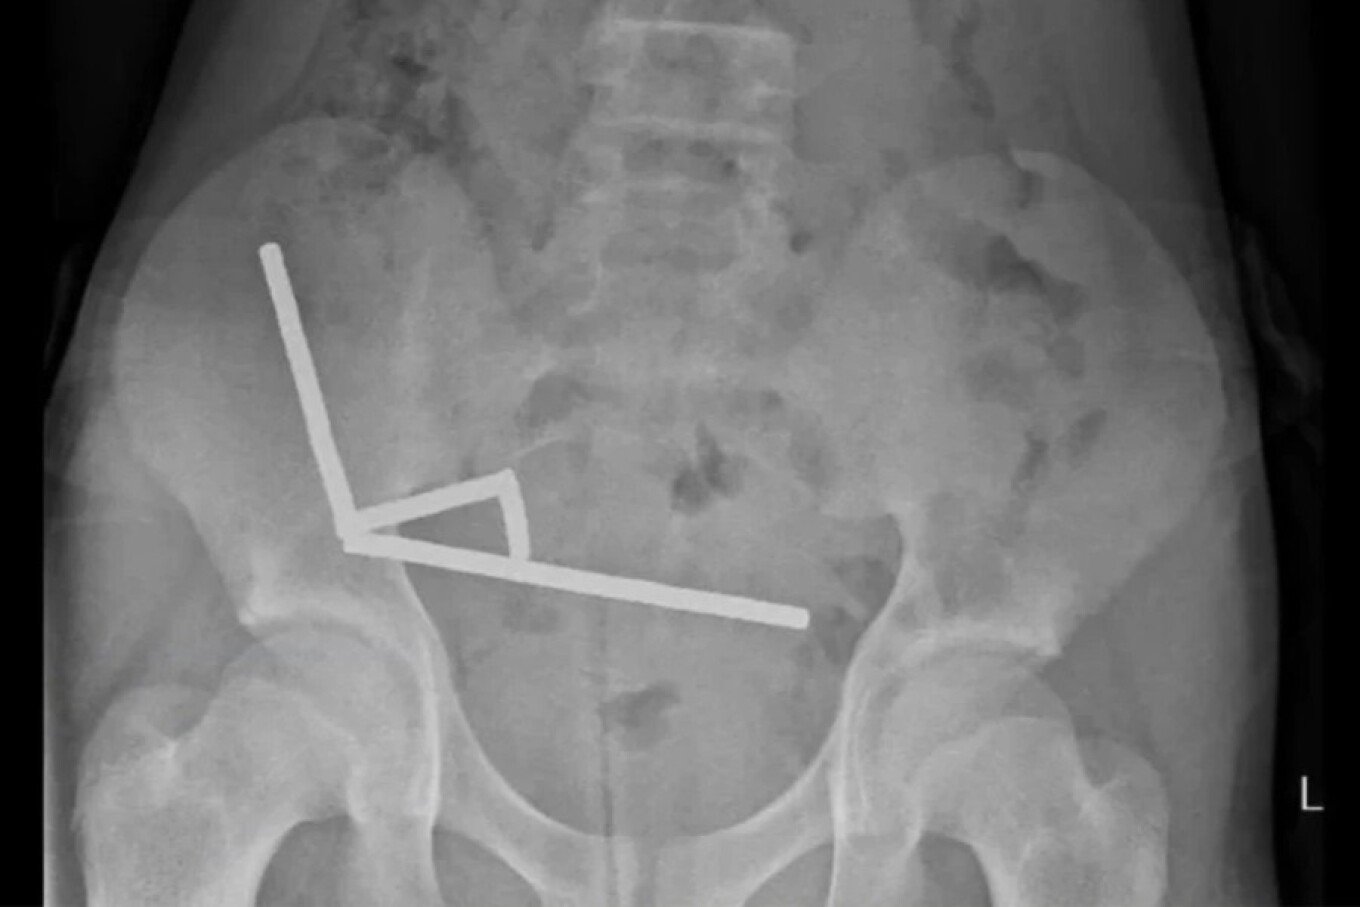

Rrezet X treguan se magnetet ishin grumbulluar në katër vija të drejta brenda zorrëve të fëmijës. Ato ishin të vendosura në pjesë të ndara të zorrëve dhe ishin ngjitur së bashku nga forcat magnetike.

Mjekët thanë se presioni nga magnetët kishte shkaktuar nekrozë në katër zona të zorrës dhe cekumit të djalit, i cili është pjesë e zorrës së trashë. Kirurgët ndërhynë për të hequr indin e vdekur dhe për të rimarrë magnetët.